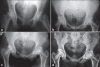

Materials and methods: The article comprises of the retrospective study of 31 patients of osteonecrosis of femoral head in stage II and III treated with core decompression and vascular pedicle grafting by using part of iliac crest with deep circumflex iliac vessels from January 1990 to December 2005. The young patients with a mean age 32 years (18-52 years) with a minimum follow-up of five years were included for analysis. Sixteen patients had osteonecrosis following alcohol abuse, 12 patients following corticosteroid consumption, 3 patients had idiopathic osteonecrosis. Nine patients were stage IIB, and 22 patients were stage IIIC according to ARCO's system. The core decompression and vascular pedicle grafting was performed by anterior approach by using part of iliac crest with deep circumflex iliac vessels.

Results: Digital subtraction arteriography performed in 9 patients at the end of 12 weeks showed the patency of deep circumflex artery in all cases, and bone scan performed in 6 other patients showed high uptake in the grafted area of the femoral head proving the efficacy of the operative procedure. Out of 31 patients, only one patient progressed to collapse and total joint replacement was advised. At the final follow up period of 5-8 years, Harris Hip Score improved mean +/- SD of 28.2 +/- 6.4 (p < 0.05). Forty-eight percent of patients had an improvement in Harris Hip Score of more that 28 points.